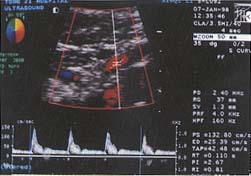

仪器与方法 仪器选用Diasonics Gate-Way ⅡD型电脑彩色多普勒诊断仪,超宽频凸阵探头,频率范围3.5~5MHz,所得资料经仪器光盘存储并录像。所有患者均前晚8时至第二天上午检查前禁食,取仰卧位,通过不同适当断面检测肝内病变的二维及血流信号后,放大显示肝总动脉(CHA)纵轴,将取样点尽量放在靠近肝总动脉的起始处(距起始点1.5cm以内),并测其内径,多普勒取样容积调至稍小于管腔(约为管腔的2/3),取样角度控制在60°以下,摒气获得满意频谱后,测时间平均速度(TAV),由仪器自动测出CHA的血流量,然后自动或手动测定PS、ED、RI。门静脉测量取肝门部门脉主干,均于呼吸末屏气后测量,具体方法同CHA。肠系膜上动脉(SMA)测量取样点位于距起始部约2cm处,方法同CHA。全部测量重复三次以上取平均值,所测频谱为显示好且至少显示三个以上心动周期(见图1~3)。

图1 在肝门部门脉主干测定

, 百拇医药

门脉的各项血流参数